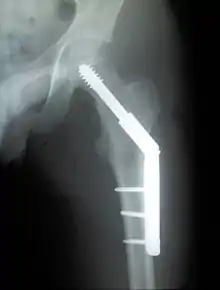

Trochanteric fracture

A trochanteric fracture, below the neck of the femur, has a good chance of healing.

Closed reduction may not be satisfactory and open reduction then becomes necessary.[42] The use of open reduction has been reported as 8-13% among pertrochanteric fractures, and 52% among intertrochanteric fractures.[43] Both intertrochanteric and pertrochanteric fractures may be treated by a dynamic hip screw and plate, or an intramedullary rod.[42]

The fracture typically takes 3–6 months to heal. As it is only common in elderly, removal of the dynamic hip screw is usually not recommended to avoid unnecessary risk of second operation and the increased risk of re-fracture after implant removal. The most common cause for hip fractures in the elderly is osteoporosis; if this is the case, treatment of the osteoporosis can well reduce the risk of further fracture. Only young patients tend to consider having it removed; the implant may function as a stress riser, increasing the risk of a break if another accident occurs.